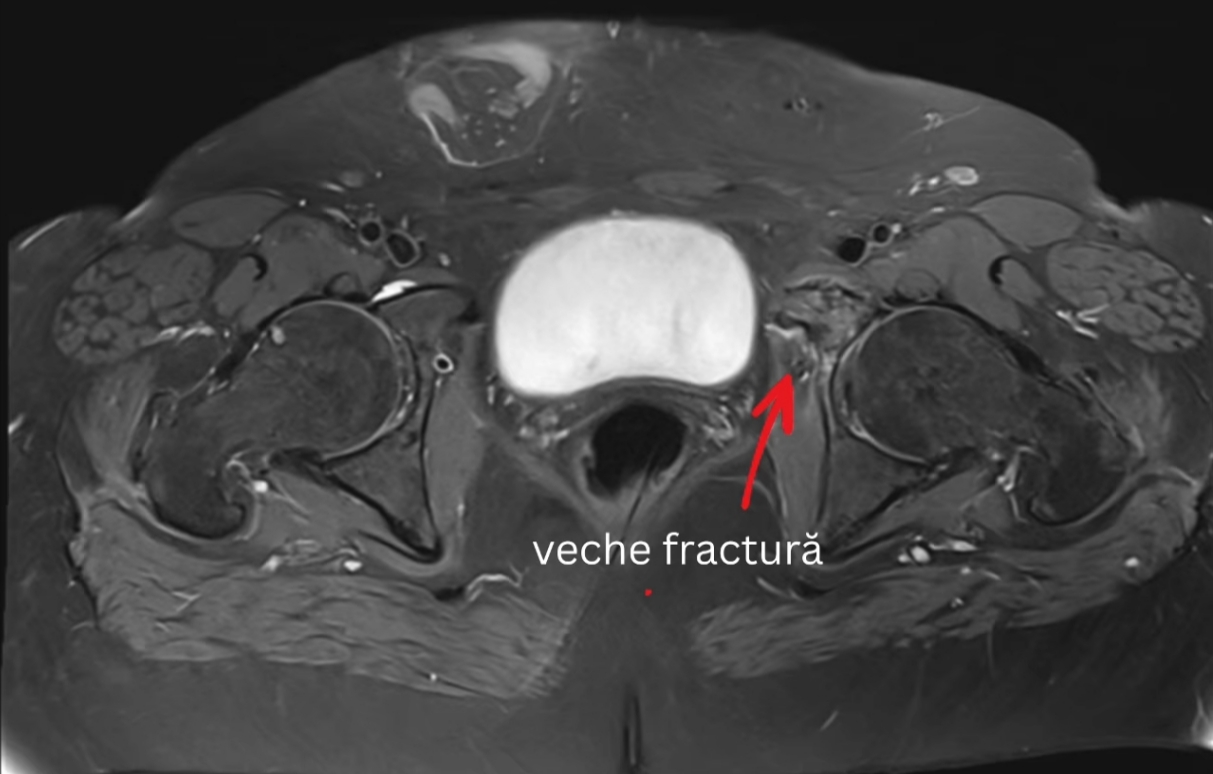

Caz real care ilustrează eficiența aparatului: O pacientă de 60 de ani, cu traumatisme anterioare, a continuat să acuze dureri severe, deși examenul CT anterior nu a evidențiat nicio fractură. RMN-ul de la Medical One a relevat clar focare de fractură și edem osos, permițând medicilor să stabilească tratamentul corect și să grăbească recuperarea.

În astfel de cazuri, RMN-ul de înaltă rezoluție face diferența între incertitudine și diagnostic precis, oferind pacientului șansa la o recuperare corectă și rapidă.